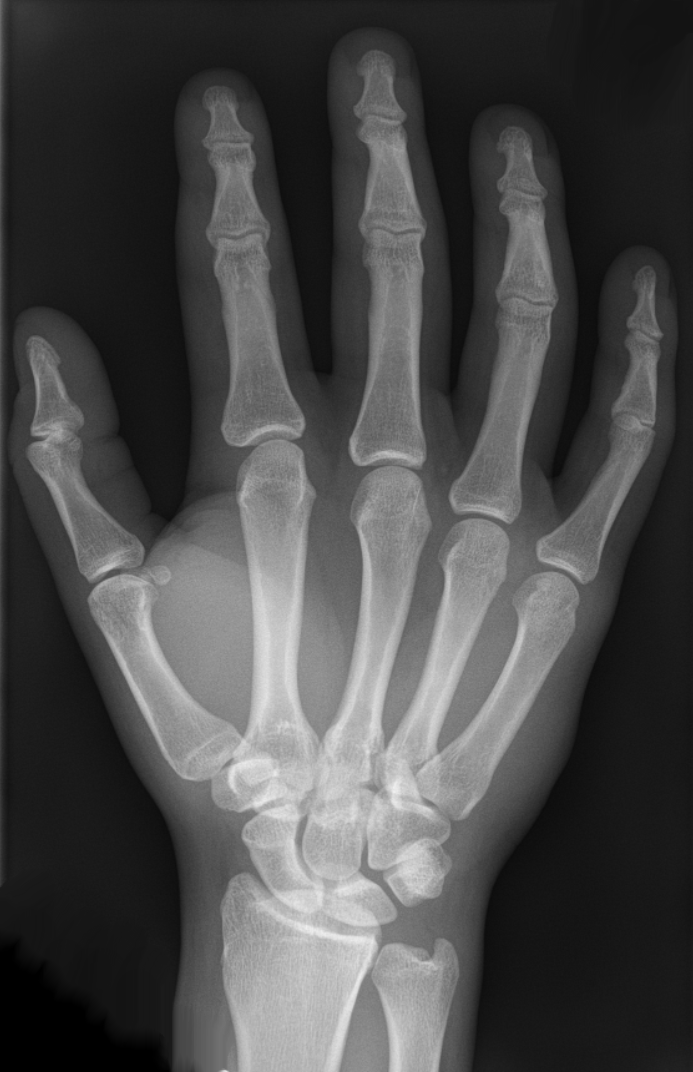

Just look at the anatomy here: fist vs cranium.

The fist is a great

weapon. Just don’t run your fist into

anything structurally stronger than it and you’ll be ok.